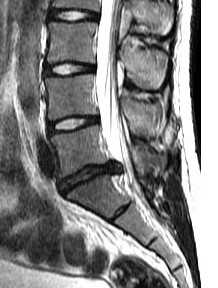

МРТ позвоночника. Сагиттальная Т2-взвешенная МРТ, срединный срез поясничного отдела. Показана нумерация позвонков, измерения позвоночного канала (черная линия). Т- дуральный мешок с ярким ликвором. L- желтая связка. Sacrum - крестец. D - межпозвоночный диск. Голубым выделен остистый отросток, желтым - тело позвонка, Голубые точки - ход корешков.

После того, как появилась ясность в способе получения МРТ изображений позвоночника, надо понять какие анатомические структуры видны. Счет позвонков ведется разными способами - сверху от зубовидного отростка С2 (осевой позвонок), от бифуркации трахеи Т5 ( пятый грудной, с погрешностью на 1 позвонок) или снизу от L5 (последний поясничный), также не исключена погрешность на 1 позвонок в связи люмбализацией или сакрализацией. Анатомия позвоночника в МРТ изображении представлена в нашей другой статье. На серии сагиттальных Т2-взвешенных МРТ позвоночника видны асе основные структуры, причем удается проследить ход корешков конского хвоста. В поясничном отделе он идет под углом вниз и выходит через межпозвоночное отверстие нижележащего позвонка. Аксиальные (поперечные) МРТ срезы всегда делаются вдоль межпозвоночного диска, то есть с учетом нормальных или патологических изгибов позвоночника. Они наиболее удобны для оценки состояния дугоотростчатых суставов. При МРТ позвоночника в поперечной плоскости МРТ срезы часто делают на разных уровнях для лучшей визуализации состояния корешков по их ходу - в дуральном мешке, затем боковом кармане дурального мешка, далее в межпозвоночном отверстии и, наконец, после выхода из него. Таким образом, в поперечном МРТ срезе позвоночника через межпозвоночное отверстие на поясничном уровне можно видеть отрезки сразу двух корешков - вышележащего на выходе из отверстия, и нижележащего в боковом кармане.